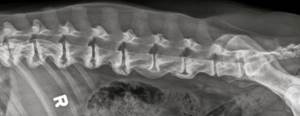

Для диагностики спондилеза необходимо сделать рентгенограмму поясничного отдела позвоночника. Довольно часто спондилез определяется при рентгенографическом обследовании для выявления других патологий.